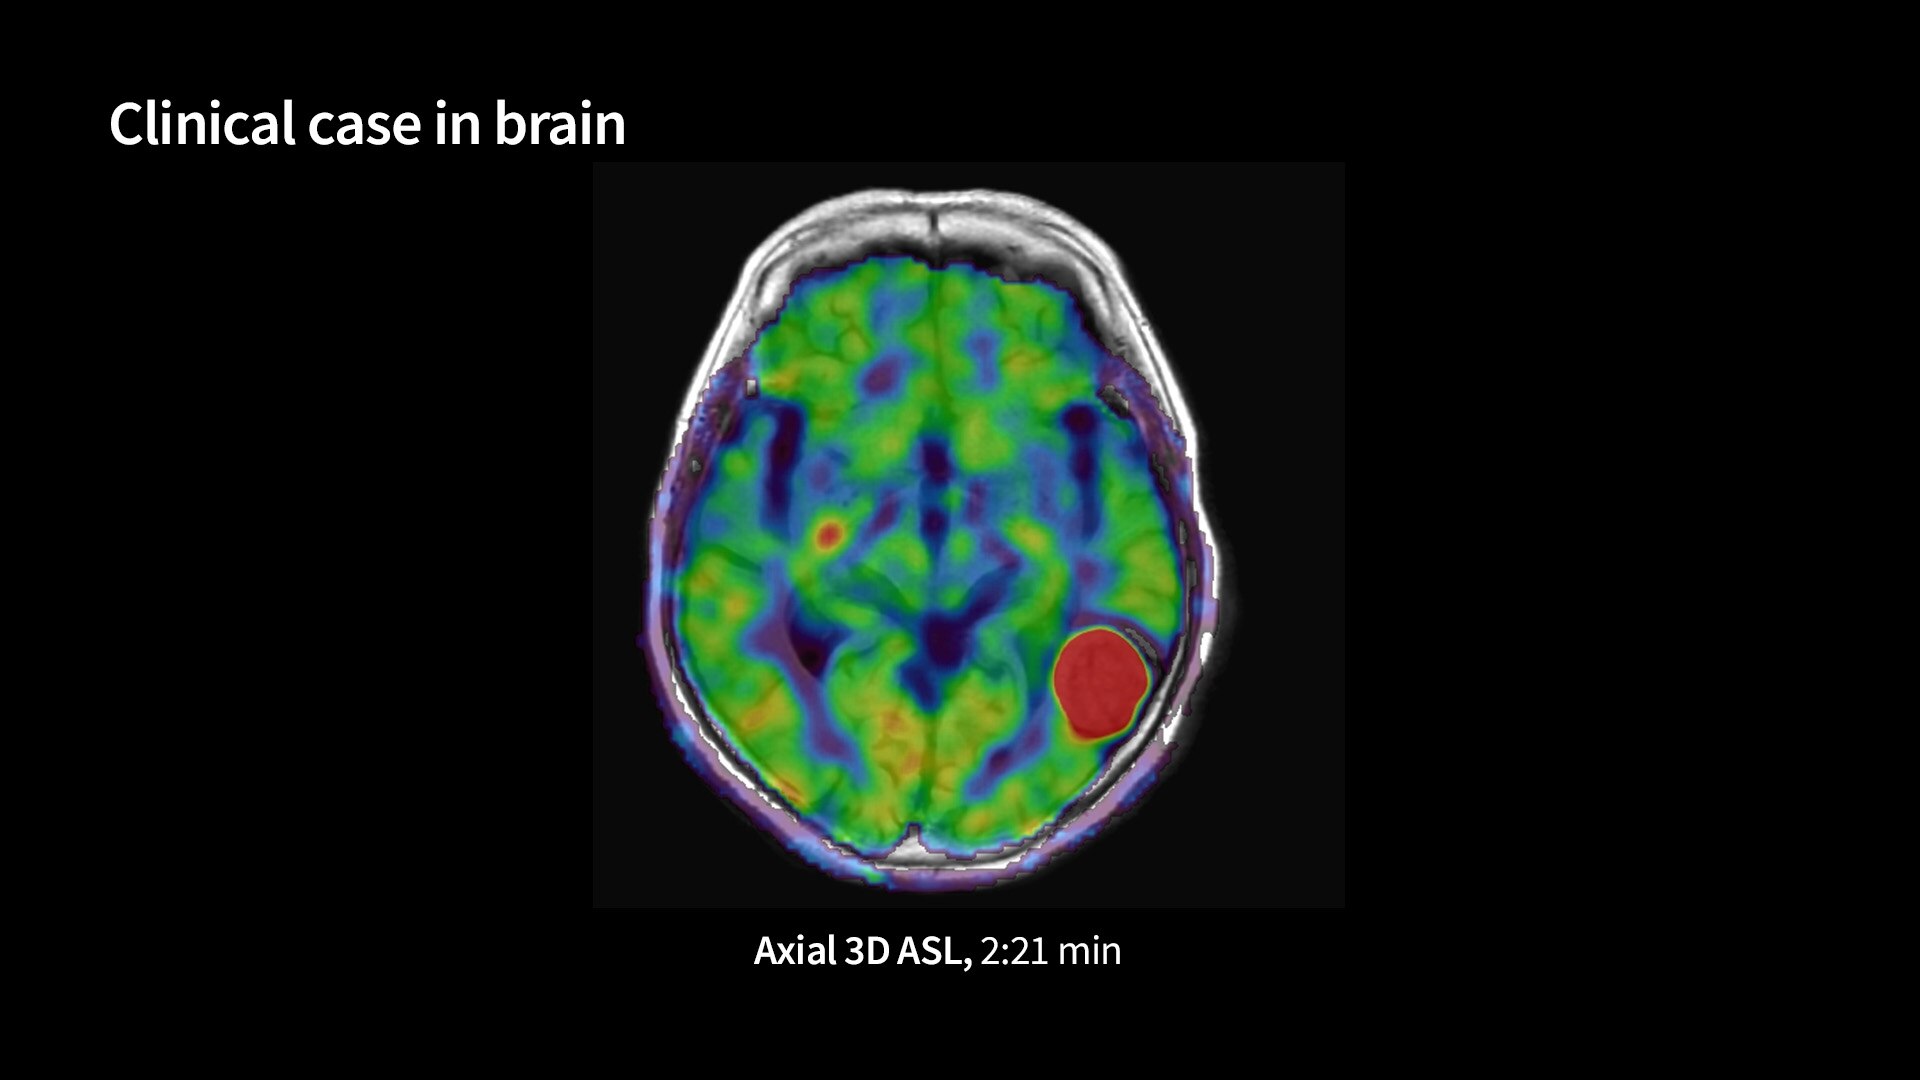

3D-Arterial-Spin-Labeling3DSpin1040-x-585

Read case study ico-caret-right